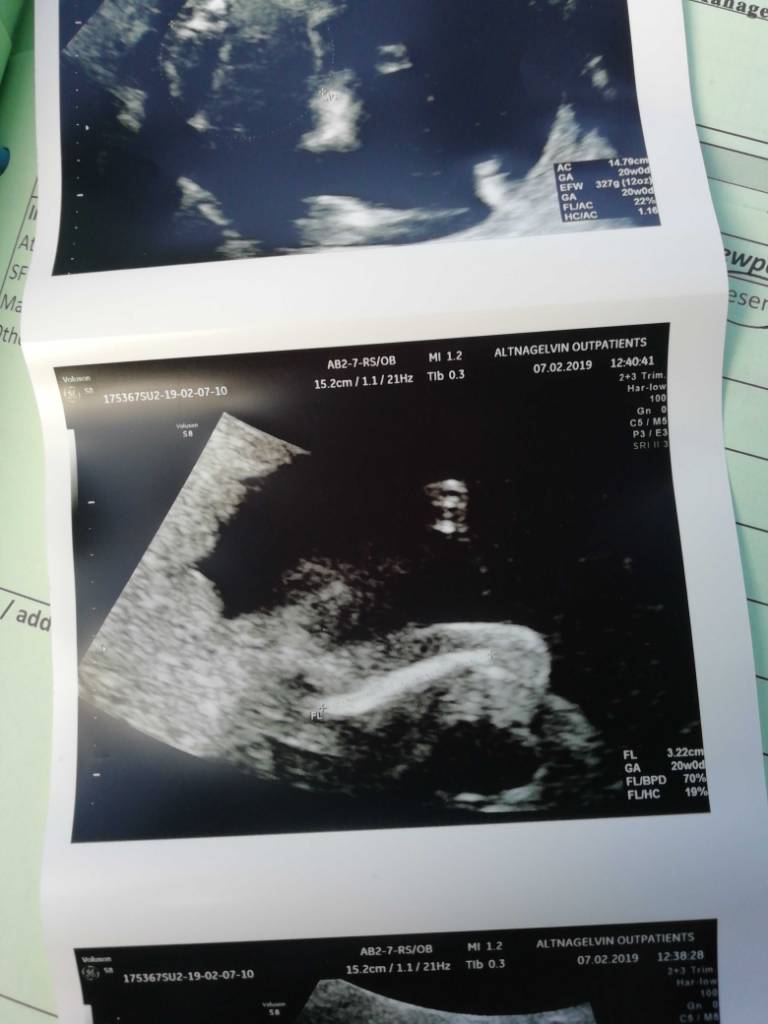

Szacowana waga 321g :) 20t2d

HC trochę mniej niż wiek ciąży ale na razie kazali nie panikowac. Jutro polowkowe